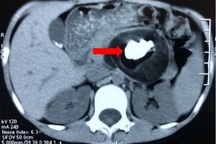

Theo người nhà, trẻ được đưa bệnh viện chỉ để kiểm tra lại và mổ amidan. Tuy nhiên, kết quả chụp X-quang có hình ảnh tổn thương giáp đốt sống bên phải, chụp phim nghiêng thấy nằm hoàn toàn cạnh cột sống.

Ngay sau đó, bác sĩ đề nghị chỉ định chụp MRI và hội chẩn kết quả cùng chuyên gia tuyến Trung ương. Trẻ được chẩn đoán mắc u thần kinh (schwannoma).